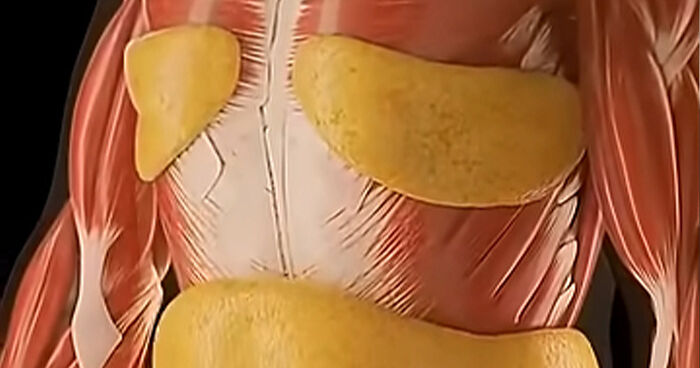

The human body is the best work of art.